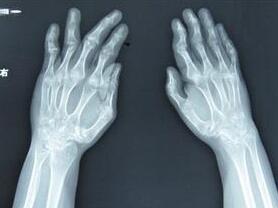

(图:X线下叶女士双手示意图)

体格检查:双手手指变形严重,双腕,双肘肿胀压痛,左肩关节不能上举,压痛明显,双膝关节肿胀,膝关节伸不直,下肢肌肉萎缩,不能站立。

辅助检验:血沉 85mm/h ,血小板 531 ×109/L 。诊断为类风湿性关节炎。